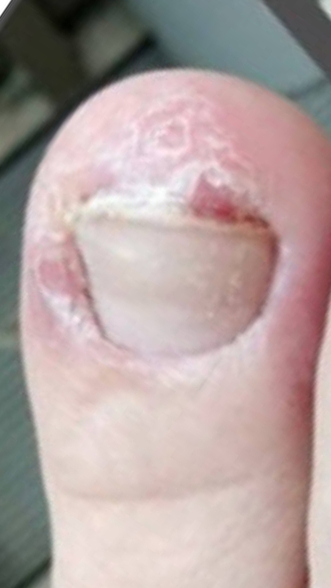

Онихолизис

После полученной механической травмы и образования субнегтевой гематомы произошло отслоение ногтя (онихолизис). Новая ногтевая пластина стала образовываться неправильно и кожный валик мешал её прорастанию.

Назначено: Зачистка ногтя у подолога, 2 процедуры 1 р/мес; ФДТ с ФС REVIXAN Derma PRO - 5 процедур 1 раз в 3-5 дней.

Ониходистрофия, онихорексис нарушение ороговевания + снижение заживления на фоне осложненного анамнеза (СД 2 типа)

Назначено: Обработка + 2 процедуры ФДТ REVIXAN